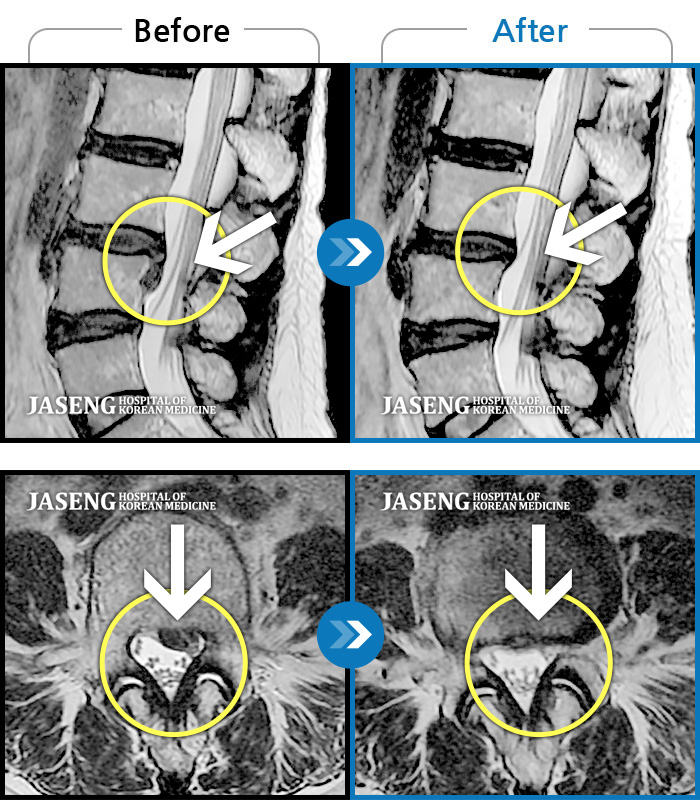

MRI 치료사례

좌측 허리와 골반으로 통증이 있었다.